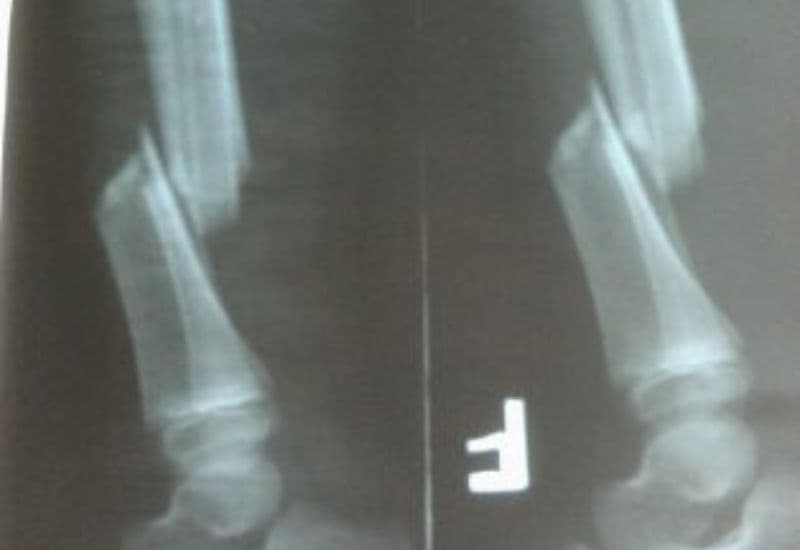

Hình ảnh gãy xương cẳng chân trên phim chụp X quang.

Gãy xương cẳng chân là tình trạng xương ở khu vực cẳng chân bị gãy, nứt hoặc vỡ. Cẳng chân gồm hai xương chính là xương chày và xương mác. Trong đó, xương chày lớn và khỏe hơn, có vai trò quan trọng trong việc chịu lực khi di chuyển. Xương mác mỏng và dài hơn, đóng vai trò hỗ trợ.